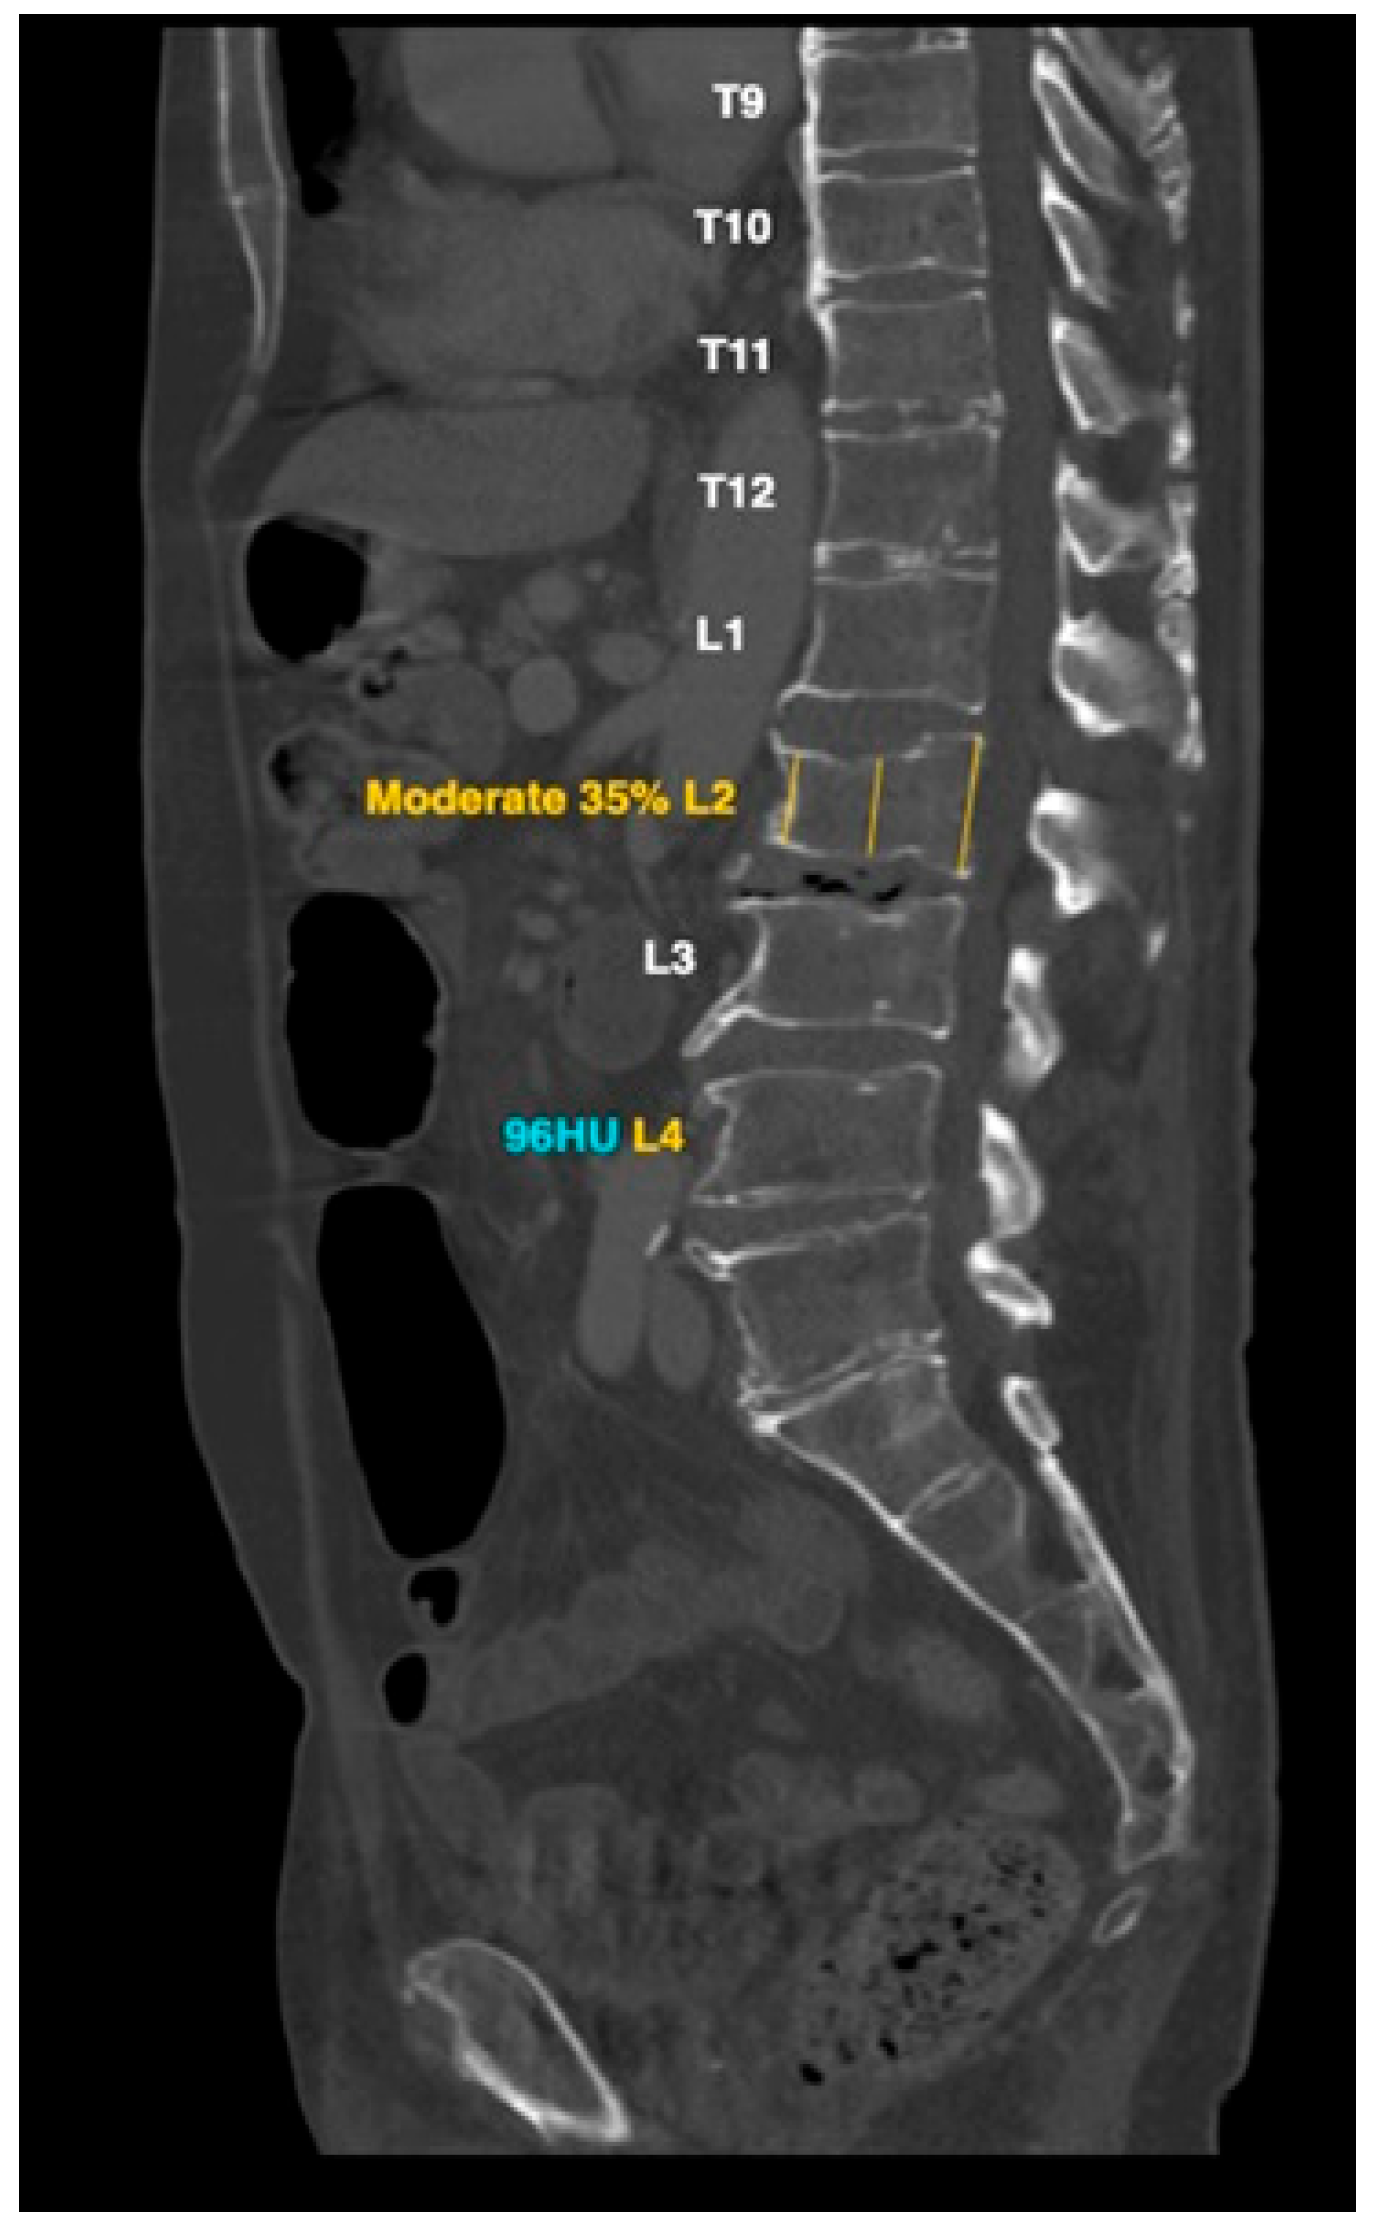

- Burns, J.E.; Yao, J.; Summers, R.M. Vertebral Body Compression Fractures and Bone Density: Automated Detection and Classification on CT Images. Radiology 2017, 284, 788–797. [Google Scholar] [CrossRef]